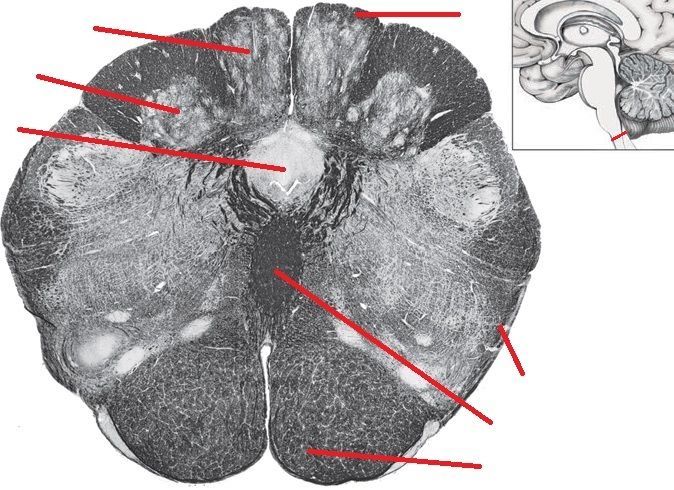

Question

Rostral Medulla

b1b0b30c-8fd1-450e-a09d-d976803adfda (image/jpeg)

Answer

Inferior Cellebellar Peduncle

Inferior Olivary Nucleus

Anterolateral System

Medial Lemniscus

Pyramid